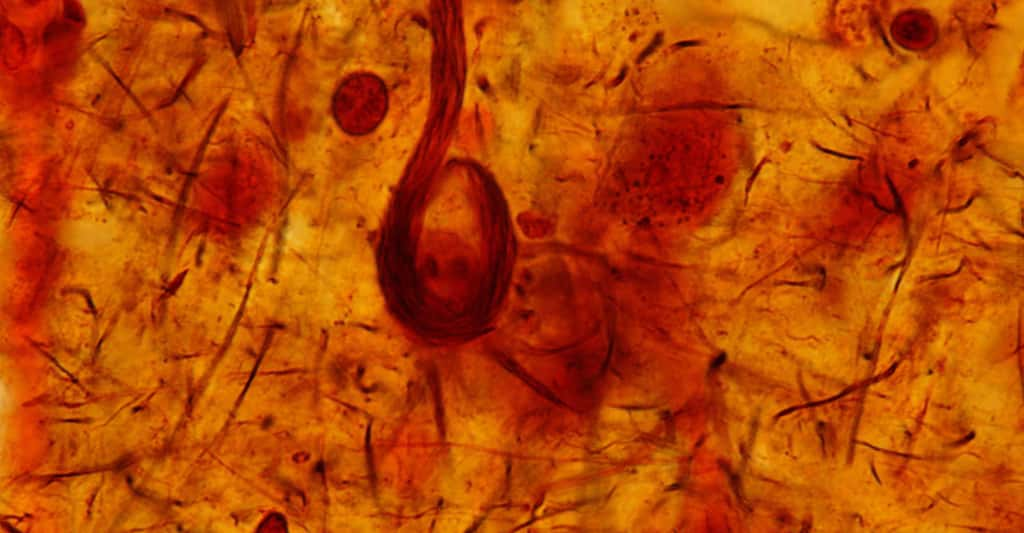

Décryptage scientifique de la maladie d'Alzheimer. © Lightspring - Domaine public